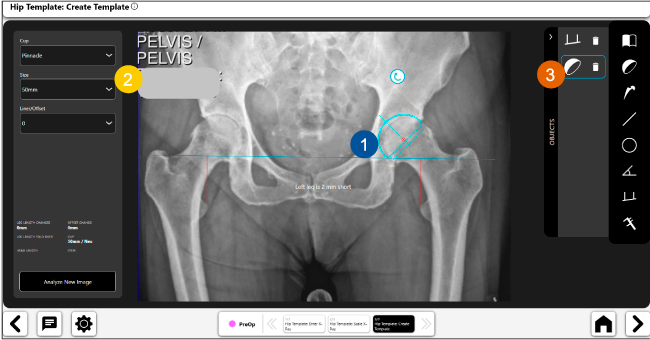

Planeación preoperatoria mediante la creación de plantillas digitales para reemplazo de cadera y análisis intraoperatorio

Disponibilidad de plantillas digitales de cadera.

Expediente histórico y personalizado, optimiza la planeación con el calendario de casos realizados en Velys TM y utiliza los íconos interactivos para una rápida revisión.

Espacio colaborativo: puede compartir los casos entre cirujanos y sus equipos mediante la funcionalidad de intercambio de información.

Anotaciones digitales y herramientas de análisis de longitud de pierna.